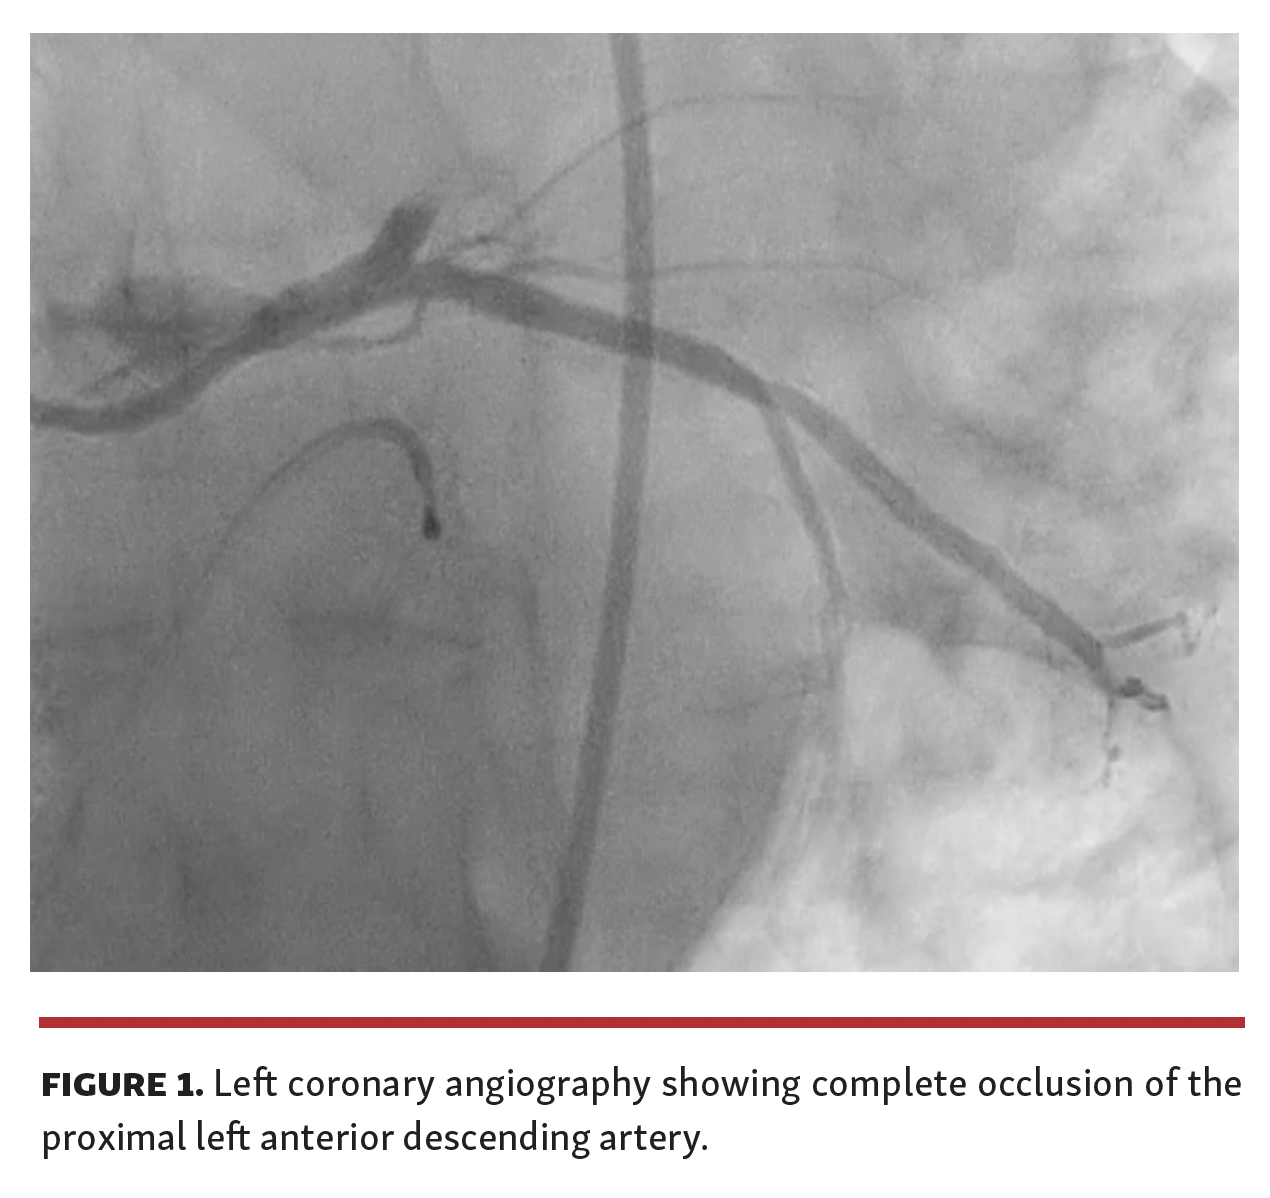

A 69-year-old male was referred to our cath lab for primary percutaneous coronary intervention (PCI) due to acute anterior ST-segment elevation myocardial infarction. The door to balloon time was about 8 hours. Left coronary angiography revealed acute occlusion of the proximal left anterior descending (LAD) artery (Figure 1 and Video 1). We immediately performed primary PCI throughout thrombus aspiration (Figure 2 and Video 2) followed by implantation of a 3 x 18 mm drug-eluting-stent (Figure 3 and Video 3). Control angiography showed no reflow (Figure 4 and Video 4). At the end of the percutaneous procedure, an abrupt clinical deterioration manifested with sudden hypotension. Transthoracic echocardiogram evidenced acute cardiac tamponade and we attempted emergency percutaneous under xiphoid pericardiocentesis. Failure to resolve cardiac tamponade and persistent hemorrhage obliged us to perform surgical subxiphoyd pericardial incision. However, the constant supply of blood from the pericardium and the development of cardiogenic shock state led us to suspect cardiac laceration. An emergency sternotomy was immediately performed.